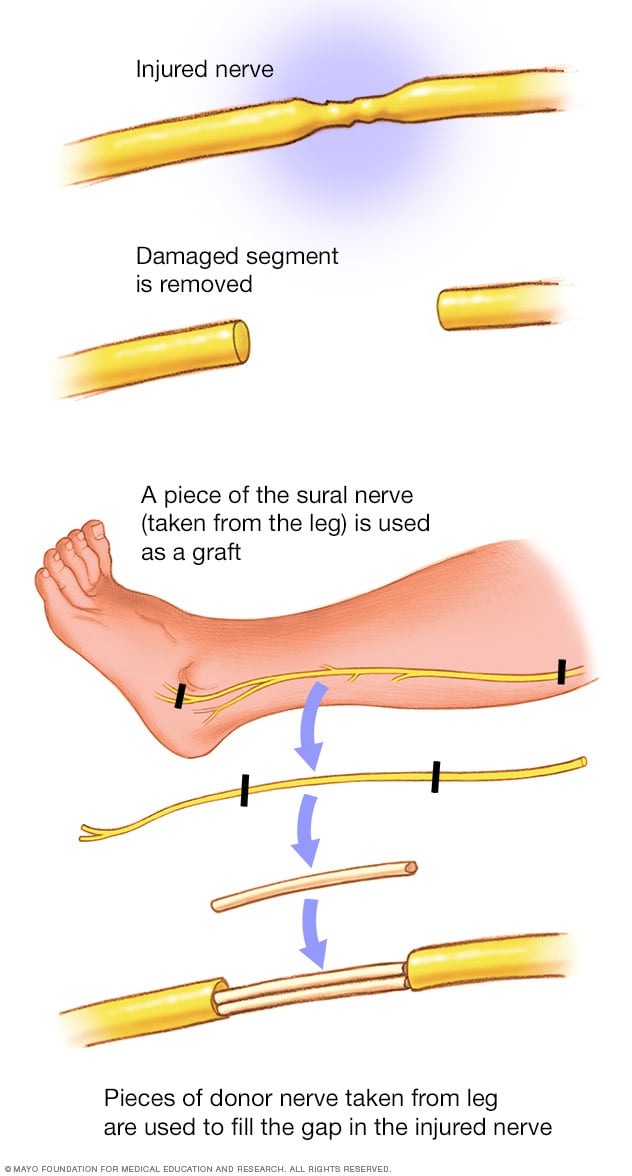

How to repair nerve damage. Clinically relevant anatomy nerve regrowth in the peripheral nervous system is dependent on the type of injury. Surgical intervention with nerve grafting is necessary to repair the injury. Surgical nerve repair involves exploration of the injured nerve and removal of injured tissue or scar from the nerve endings.

Ct or mri scans can look for herniated disks, pinched nerves, also called compressed nerves, growths or other problems affecting the blood vessels and bones. Boeing tries to build a ‘neutral’ nerve center the structural weaknesses in boeing’s planemaking flow can actually be quite neatly traced to strategic missteps that. Current therapies to repair nerve damage involve transplanting the patients' healthy nerves to repair damage or implanting an artificial nerve guidance conduit.

Surgeries that occur later than that have lower success rates. The nerves can grow back to their muscle or skin areas, but this process can take several months, and the messages between the. Functional disability due to nerve lesions is intertwined with the.